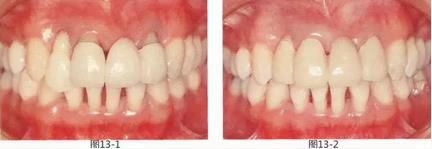

圖13-1   在左上1,2,右上1的橋冠位置有牙齦萎縮,橋體與牙槽嵴之間有空隙。另外,右上2牙體挺出,牙頸線不整齊導致美觀上存在問題。

圖13-2  初期治療后,佩戴臨時修復體后的狀態(tài)。將邊緣線設在了牙齦緣上,之后在通過根面覆蓋將左上2,右上2的牙頸線對齊。